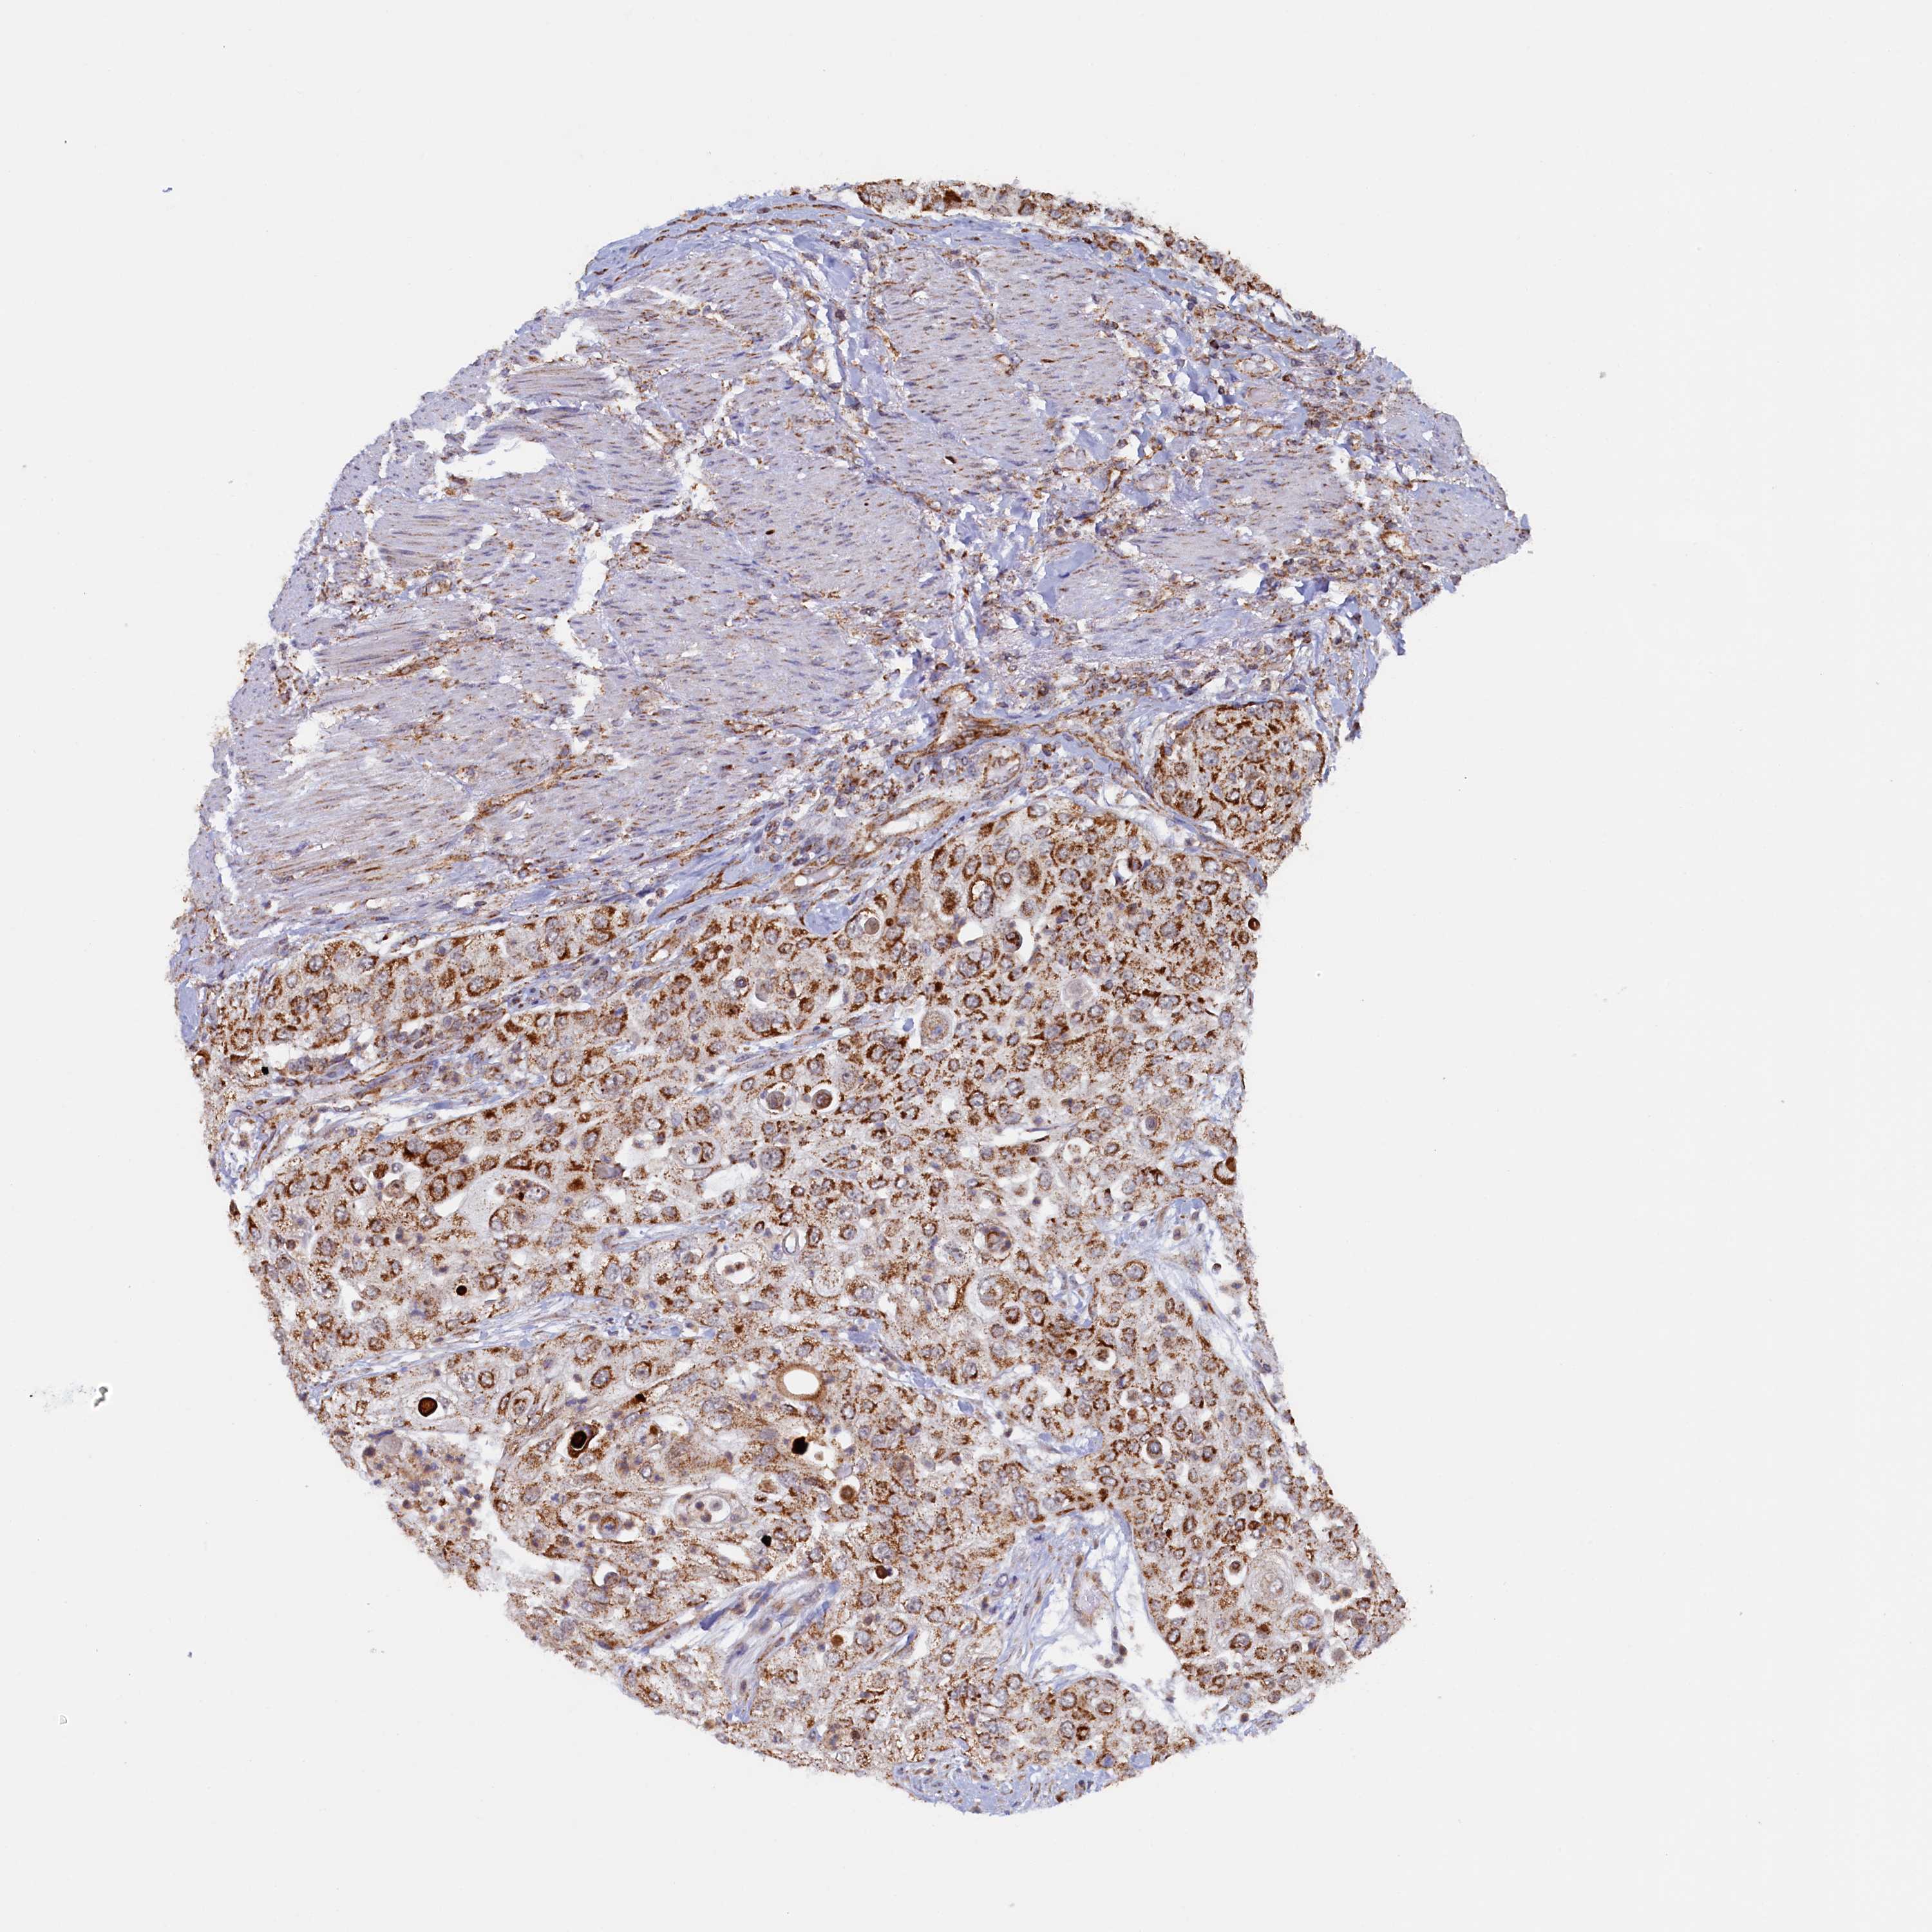

UROTHELIAL CANCER - Protein expressioni

A mouse-over function shows sample information and annotation data. Click on an image to view it in a full screen mode. Samples can be filtered based on level of antibody staining by selecting one or several of the following categories: high, medium, low and not detected. The assay and annotation is described here.

Note that samples used for immunohistochemistry by the Human Protein Atlas do not correspond to samples in the TCGA dataset.

Antibody stainingi

Antibody staining in the annotated cell types in the current human tissue is reported as not detected, low, medium, or high, based on conventional immunohistochemistry profiling in selected tissues. This score is based on the combination of the staining intensity and fraction of stained cells.

Each image is clickable and will lead to virtual microscopy that enables deeper exploration of all samples and also displays staining intensity scores, fraction scores and subcellular localization as well as patient and tissue information for each sample.

Antibody HPA041012

Staining

High

Medium

Low

Not detected

Intensity

Strong

Moderate

Weak

Negative

Quantity

>75%

75%-25%

<25%

None

Location

Nuclear

Cytoplasmic/membranous

Cytoplasmic/membranous,nuclear

Urothelial carcinoma, High grade

Urothelial carcinoma, Low grade